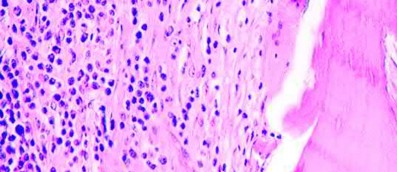

Histological analysis of the peri-articular tissue reveals aseptic lymphocytic vasculitis-associated lesions (ALVAL). What is the primary immunologic mechanism driving this specific histological response?

ALVAL (Aseptic Lymphocytic Vasculitis-Associated Lesions) is characteristic of adverse local tissue reactions (ALTR) in metal-on-metal hip implants. It is driven by a Type IV (delayed) hypersensitivity reaction to metal ions (like cobalt and chromium). This cell-mediated response involves the activation of CD4+ Th1 cells and is characterized histologically by a dense perivascular lymphocytic infiltrate, tissue necrosis, and the formation of pseudotumors, distinguishing it from the simple macrophage-mediated foreign body response seen with conventional polyethylene wear debris.